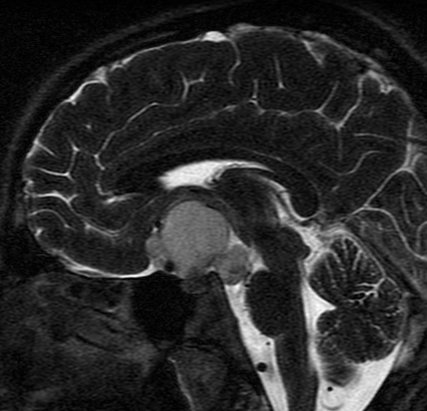

December 2005 - Craniopharyngioma

There is evidence of a lobulated extra-axial mass lesion in the suprasellar cistern. The lesion is predominantly hyperintense on the T1W images and heterogeneously hyperintense on the T2W and FLAIR images. The optic chiasm, proximal optic nerves and the pituitary stalk cannot be identified separately from this lesion. However, the pituitary gland is well identified.

Craniopharyngiomas are epithelially derived neoplasms that usually occur in the suprasellar cistern. Occasionally they occur in the sella or in the third ventricle.  They constitute approximately 3% of all intracranial tumors and show no sex predilection. Craniopharyngiomas are hormonally inactive lesions. 50% of these lesions occur in childhood or adolescence, with a peak incidence between 5 and 10 years of age. A second smaller peak is seen in the sixth decade. Patients may present with headaches and/or visual disturbances. The lesions usually exhibit a heterogeneous appearance with presence of a cystic and/or solid component. It may be hyperintense on both T1W and T2W images. The lesions may encase nearby cerebral vasculature. The solid portion may be calcified. On contrast the solid portion usually enhances.